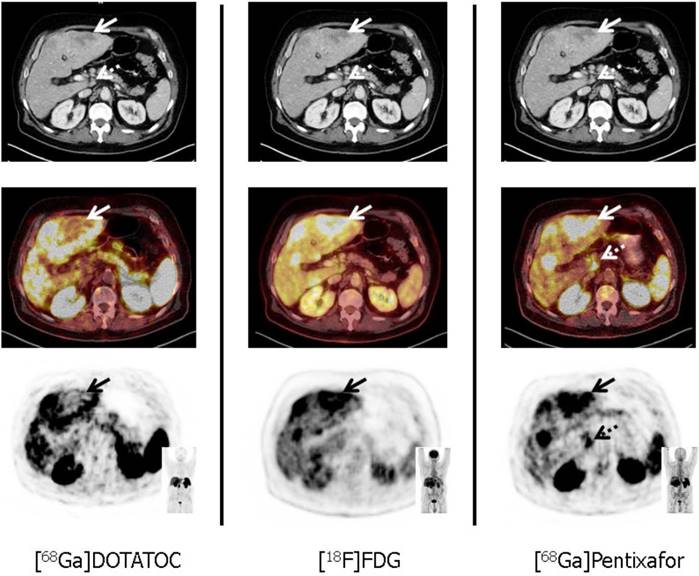

[68Ga]-Pentixafor/[177Lu]-Pentixather. The C-X-C motif chemokine receptor CXCR4 is overexpressed on the NET cell surface. Kämmerer et al. reported on an inverse expression of SSTR2 and CXCR4 in G1 to G3 NET in surgical GEP-NET samples with an upregulation of CXCR4 and a downregulation of SSTR occurring with increasing tumor grade [56]. These histological findings were further corroborated in vivo by using the novel CXCR4-targeting imaging probe [68Ga]-Pentixafor. In a triple-tracer approach ([68Ga]-Pentixafor vs. [68Ga]-DOTATOC vs. 2-deoxy-2-18F-fluoro-D-glucose ([18F]-FDG)), the majority of [68Ga]-Pentixafor-positive subjects showed a Ki67 of > 85% with concordant high glycolytic activity (assessed by [18F]-FDG PET) and markedly decreased (or even absent) SSTR-expression. Thus, endoradiotherapy with [177Lu]-Pentixather may be applicable in highly proliferative G3 NET, e.g. after failure of 1st or 2nd-line treatments [12]. However, this “proof-of-concept“ study definitively needs further research enrolling a larger patient cohort, in particular as other therapies may alter CXCR4 expression on the cell surface [57]. Figure 2 displays a triple-tracer approach using [18F]-FDG PET, [68Ga]-DOTATOC and [68Ga]-Pentixafor in a G3 NET patient with a Ki67 > 90%. Tumor heterogeneity in a liver lesion (no SSTR-expression, but increased glycolytic activity and upregulation of CXCR4) can be appreciated.

Figure 2

Tumor heterogeneity in a patient with a G3 gastric NET and liver metastases in a 67 year old patient suffering from gastric NET with liver metastases (Ki67 = 90%, G3 NET). In accordance with G3 NET, hypermetabolic hepatic metastases demonstrate loss of SSTR and up-regulation of CXCR4 expression (solid arrows). Moreover, [68Ga]-Pentixafor provides additional information on disease extent by exclusively detecting a coeliac lymph node suspicious for metastatic disease (dotted arrows). From Werner et al., Theranostics, [12].